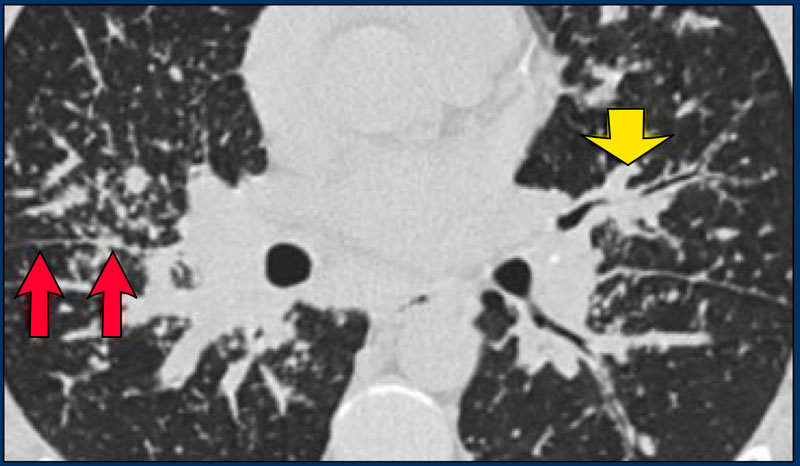

Симптом дерева в почках

Симптом дерева в почках 116 фотографий